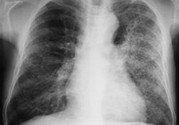

小兒肺炎的癥狀表現(xiàn)有哪些?小兒肺炎應(yīng)該怎么治療?

小兒肺炎在孩子中是很容易發(fā)生的,孩子身體免疫力比較低,容易受到傳染。那么,小兒肺炎的癥狀表現(xiàn)有哪些呢?

小兒肺炎癥狀

早期癥狀: 流清鼻涕、鼻塞、噴嚏等,也可用流淚、微咳或咽部不適,可在3~4天內(nèi)自然痊愈。開(kāi)始為頻繁的剌激性干咳,隨之咽喉部出現(xiàn)痰鳴音,咳嗽時(shí)可伴有嘔吐、嗆奶。有時(shí)淋巴結(jié)可稍腫大。呼吸表淺增快,鼻扇,部份患兒口周、指甲輕度發(fā)紺。除呼吸道癥狀外伴有精神萎靡、煩躁不安、食欲不振、哆嗦、腹瀉等全身癥狀。在嬰幼兒容易引起嘔吐及腹瀉。

晚期癥狀: 持續(xù)高熱、全身中毒等癥狀嚴(yán)重,且伴有其它臟器功能損害。伴有冷感,頭痛、全身無(wú)力、食欲銳減、睡眠不安等,不久即可因部微紅,發(fā)生皰疹和潰瘍,有時(shí)紅腫明顯,波及扁桃體,出現(xiàn)濾泡性膿性滲出物,咽痛和全身癥狀均加征,鼻咽分泌物從稀薄變成粘稠。